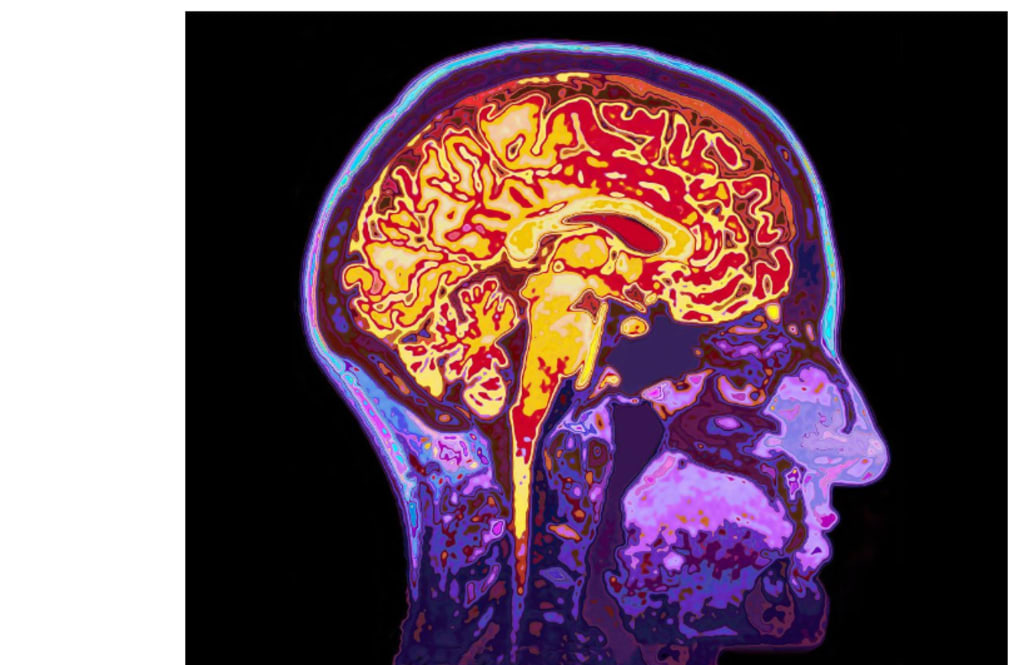

Microplastics are tiny pieces of plastic that have been found in food, water, and the air. These microplastics can now cross the blood-brain barrier and gather in deep brain regions, according to a study done on 52 donated human brains.

Experts also looked into whether specific circumstances make the accumulation of these materials worse. They observed that compared to other samples, the brains of a group of dementia patients had three to five times as much plastic fragments.

The shapes of the shards observed under an electron microscope shocked the scientists. Many were ragged, flake-like formations rather than tidy spheres. Microplastics with smooth, round shapes may interact with cells differently than those with uneven morphologies.

Particles can lodge much deeper in the frontal brain, according to the current research.